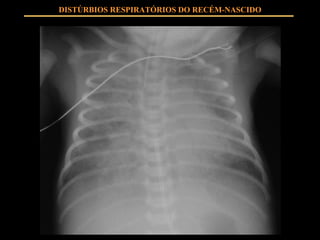

DISTÚRBIOS RESPIRATÓRIOS DO RECÉM-NASCIDO USO DE SURFACTANTE EXÓGENO: Diminui tensão superficial alveolar Mantém estabilidade alveolar

DISTÚRBIOS RESPIRATÓRIOS DO RECÉM-NASCIDO USO DE SURFACTANTE EXÓGENO: PROFILÁTICO RESGATE

DISTÚRBIOS RESPIRATÓRIOS DO RECÉM-NASCIDO USO DE SURFACTANTE EXÓGENO: DISTRESS RESPIRATÓRIO GRAVE EM PRIM 48 HS ADMINISTRAÇÃO ASSIM QUE DIAGNÓSTICO O USO DE SURFACTANTE É SEGURO É UM A TERAPIA DE ALTO CUSTO